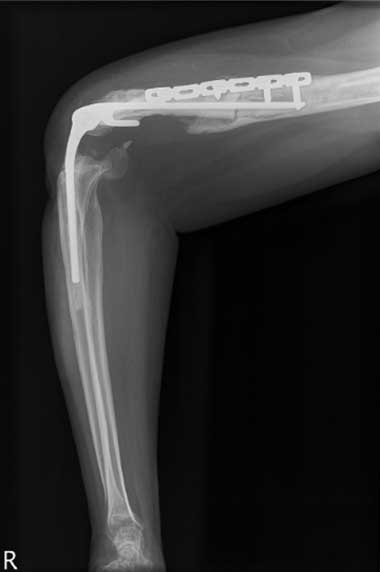

All 11 patients were taken to theatre within 24 hours of arrival at RPH and all underwent a washout and debridement. Depending on the injury, the procedures performed included open reduction and internal fixation; nerve, artery and tendon repair; and free flaps and split-skin grafting. Nine patients underwent multiple surgical procedures; 10 required open reduction and internal fixation with low contact dynamic compression plates for open fractures of the humerus, ulna and radius. The various plating procedures are illustrated in Box 2.

The most severe upper-arm injury involved Patient 7, with loss of the right distal humerus and olecranon, combined with an ulna nerve injury (Box 3). Initial treatment consisted of debridement and application of a bridging external fixator across the lost elbow joint (Box 4). This was complicated by iatrogenic radial nerve neuropraxia caused by the insertion of a Steinman pin. The external fixator was later replaced by a humeral allogeneic bone graft, an elbow prosthesis, and plate fixation of the humeral shaft (Box 5). The same patient also subsequently underwent a revision of the humeral plate procedure after a deep infection with Staphylococcus epidermidis was identified.

2 The various open reduction internal fixation (ORIF) procedures in patients with sideswipe injuries